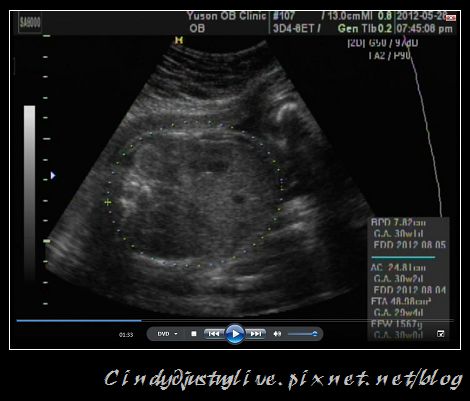

頭好壯壯1567G

之前驗出來的妊娠糖尿病,醫生說我現在是還好,因為妊娠糖尿病主要是怕小孩子會巨嬰不好生,還有就是會有低血壓的問題,巨嬰嘛,依我小孩現在的狀況來看是都很正常,而低血壓現在也沒辦法驗,只能等生下來才知道……。凹嗚~